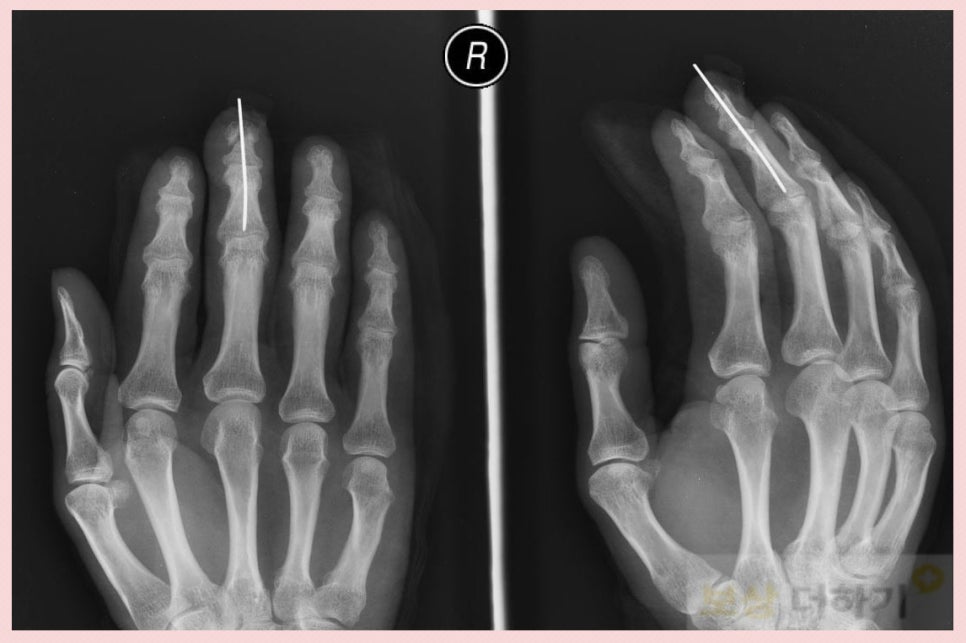

이 사고로 접합술을 받으셨습니다. 아래 사진은 강선을 이용하여 뼈를 맞추고 고정해 준 모습입니다.

보험사는 지급했을까요? 손가락이 절단된 것이니 당연히 보험금을 문제없이 받을 수 있지 않을까 생각할 수도 있는데요. 엑스레이 상 골소실이 확실치 않다는 이유로 보험금을 지급하지 않으려고 했습니다. 저희는 CT 검사 등, 다시 검토를 하여 '손가락뼈 일부를 잃었을 때' 5%​ 에 해당된다는 것을 입증하였습니다. 결국, 저희가 청구한 대로 인정을 받았고 후유장해 보험금으로 1천만 원 이상을 받을 수 있었습니다.